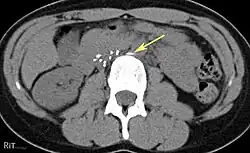

Axial CT image confirms that one of the legs (arrow) of the IVC filter has migrated out of the IVC wall into an adjacent tissue.